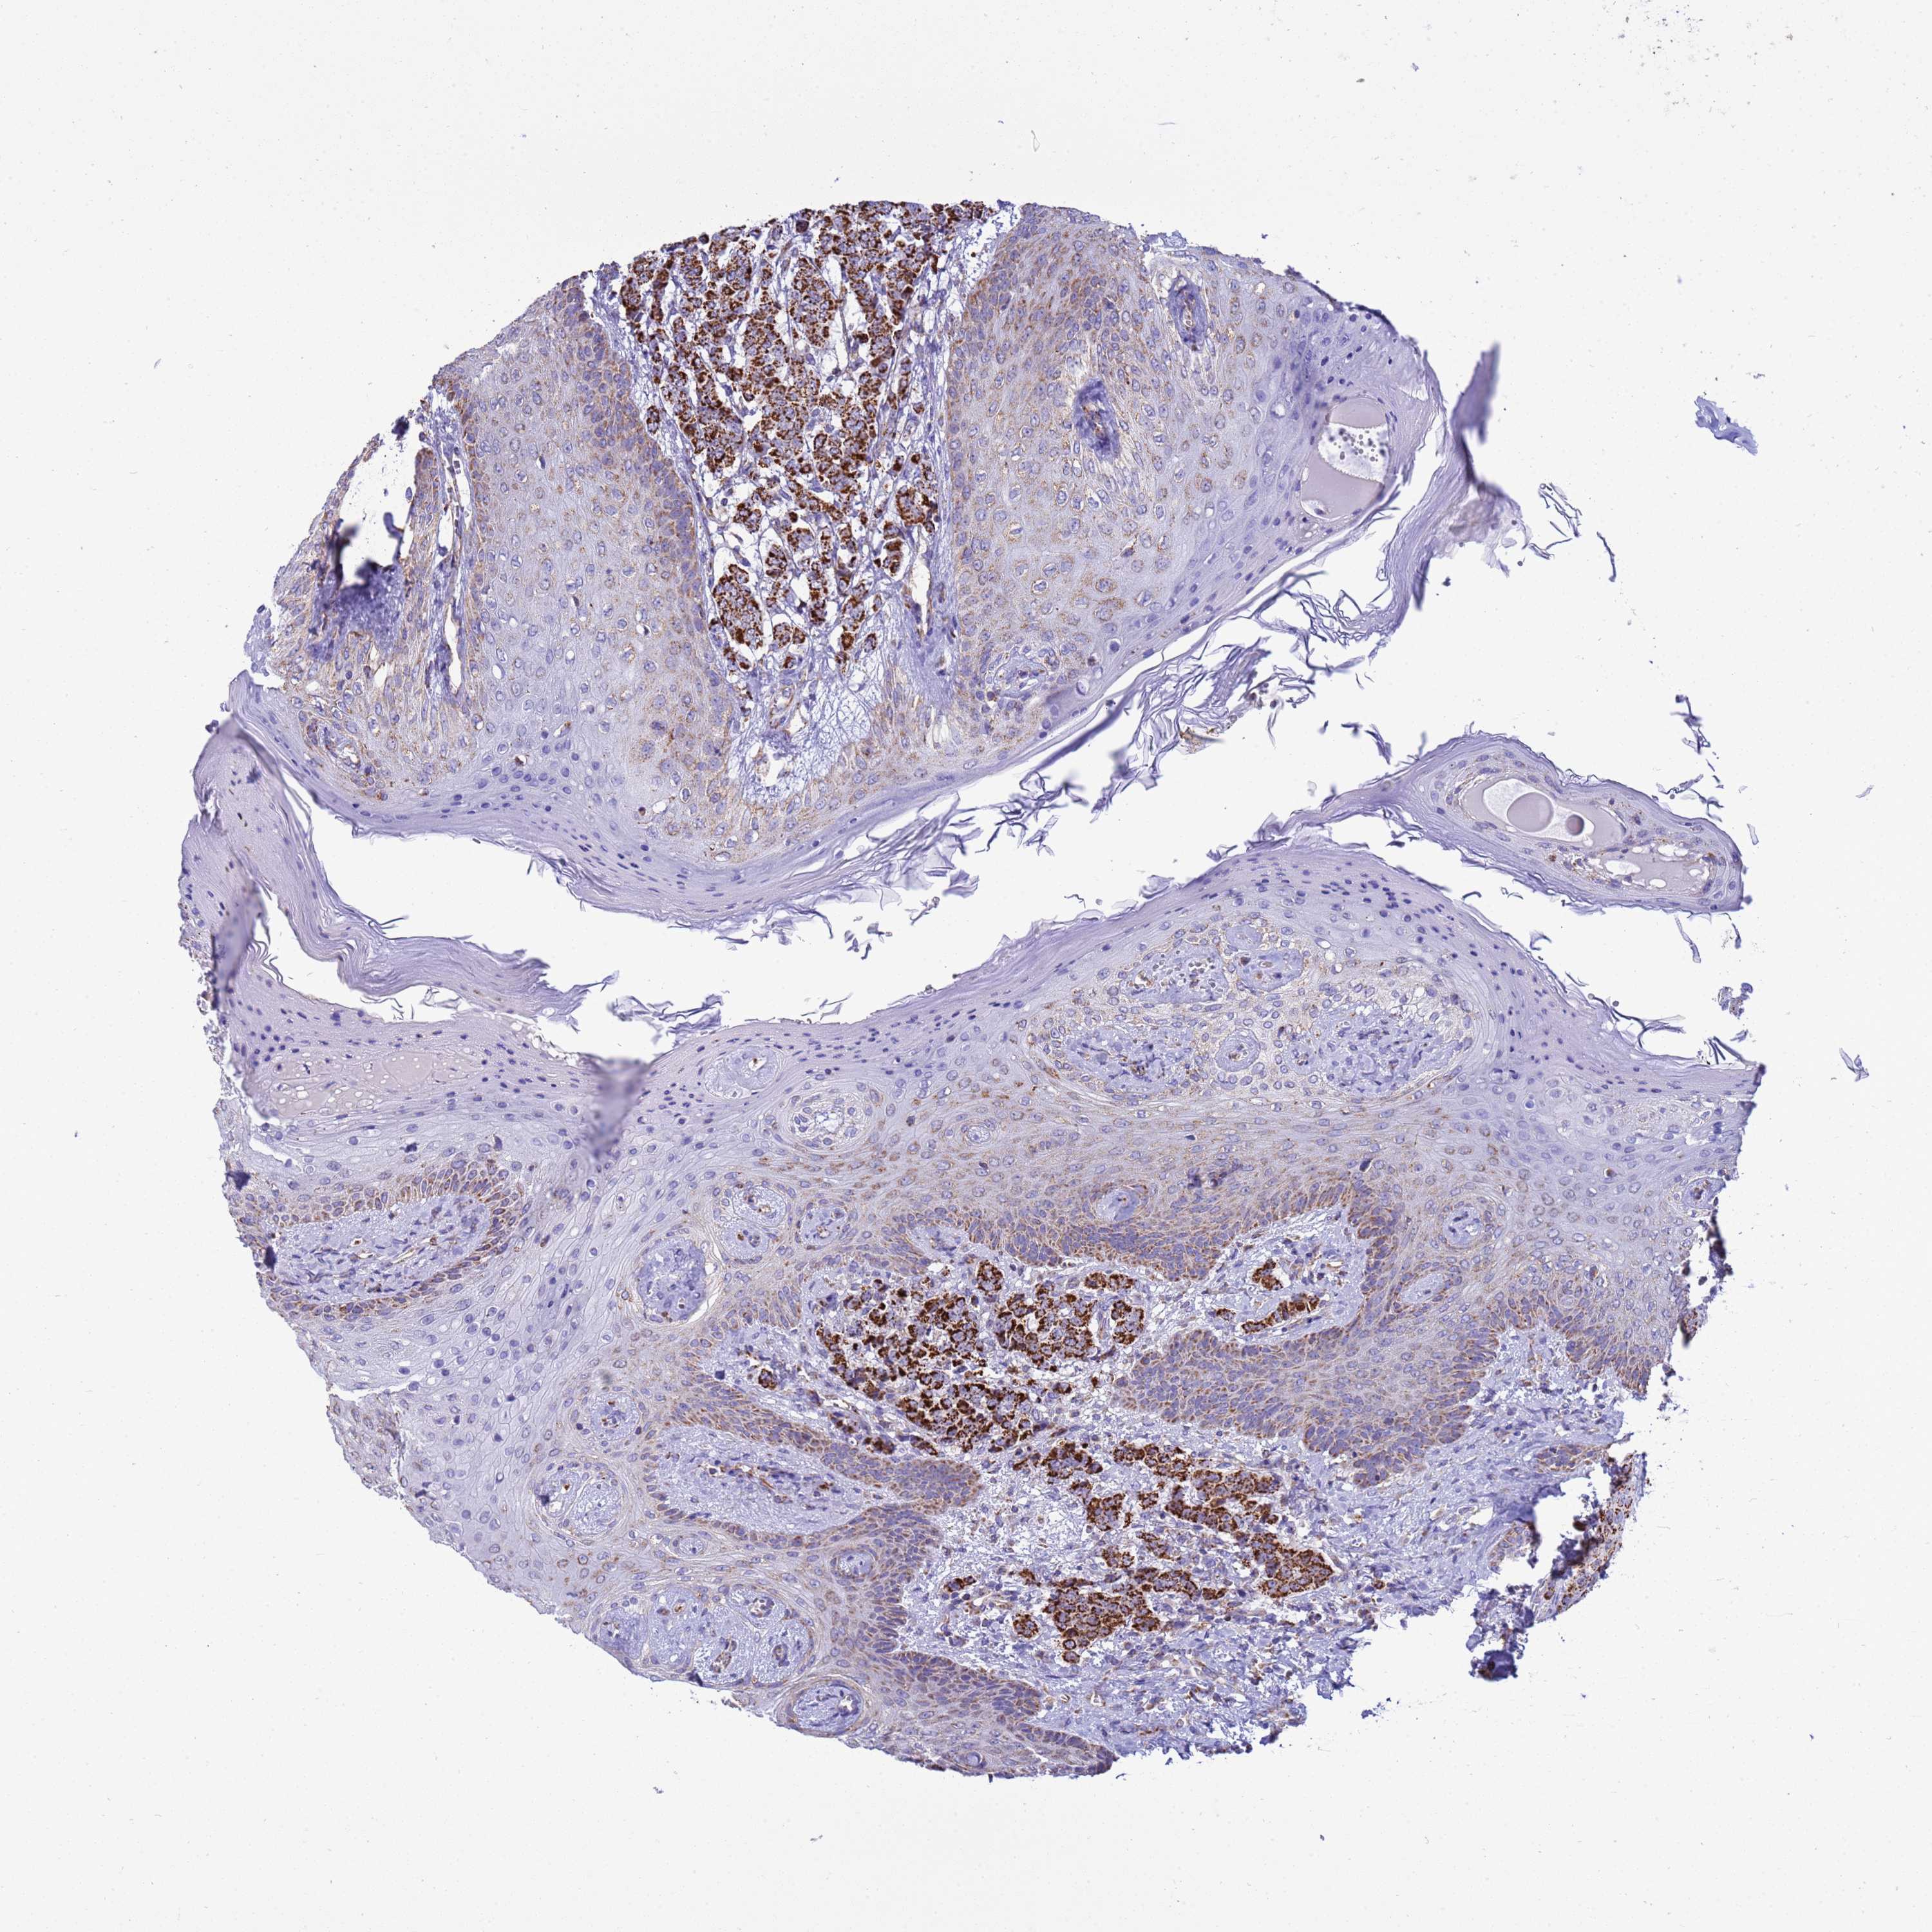

CANCER BREAST CANCER Show tissue menu

BRCA TCGA BRCA VALIDATION PROTEIN EXPRESSION